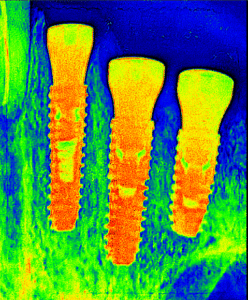

We are Offering following Types of Dental Implant

Individual tooth implant - Click

Single dental implant suitable for single missing tooth and most simplest procedure involved. It can be place immediately after removal of damaged teeth in same visit or few months after of extraction of teeth. In case of anterior tooth we can provide temporary teeth in the placed implant which need to replaced with permanent prothesis in few months.

Now a days, 3D guided dental implant become most popular to place dental implant. Because of no surgical flap need to be reflect during surgery, reduce the surgery time and minimize post surgery risks.

Depending of types of dental implant cost also varies.

Implant retained bridge - Click

Implant Retained dental bridge considered when more than two adjacent teeth are missing. Its superior to the traditional dental dental bridge as do not need to prepare natural teeth. It’s provide same aesthetic and functional capacity similar to the natural teeth.

Same procedure involved similar to single implant. We recommend 3D guided implant placement to avoid complication and more accuracy in placement.

All-On-6 & 8 Dental Implant - Click

The All-on-6 dental implant technique is a full-arch restoration method where six implants are strategically placed in the jawbone to support a fixed prosthesis, such as a full set of teeth. This approach provides a permanent solution for patients with multiple missing teeth or complete tooth loss, offering better stability and load distribution compared to All-on-4. The posterior implants are often angled to maximize bone support and avoid anatomical structures like nerves or sinuses, reducing the need for bone grafting in many cases. It restores oral function and aesthetics, enhances patient confidence, and offers a durable, long-lasting alternative to removable dentures. The procedure involves implant placement, a healing period for osseointegration (typically 3-6 months), and the final attachment of the prosthesis, making it ideal for individuals with sufficient jawbone density seeking a reliable full-mouth restoration.

All-on-4 Dental Implant -Click

The All-on-4 is another option of dental implant for full-arch restoration method where four implants are strategically placed in the jawbone to support a fixed prosthesis, providing a permanent solution for total tooth loss or multiple missing teeth. The posterior implants are angled to maximize bone contact and avoid anatomical structures like sinuses or nerves, often eliminating the need for bone grafting. This technique offers a stable, cost-effective alternative to traditional implants, restoring oral function, aesthetics, and confidence. The procedure involves implant placement, a healing period for osseointegration, and attachment of a fixed prosthesis, making it suitable for patients with limited bone density seeking a reliable, long-lasting solution. Procedure duration 3 to 6 months. We always prefer to do this procedure with 3D guide.